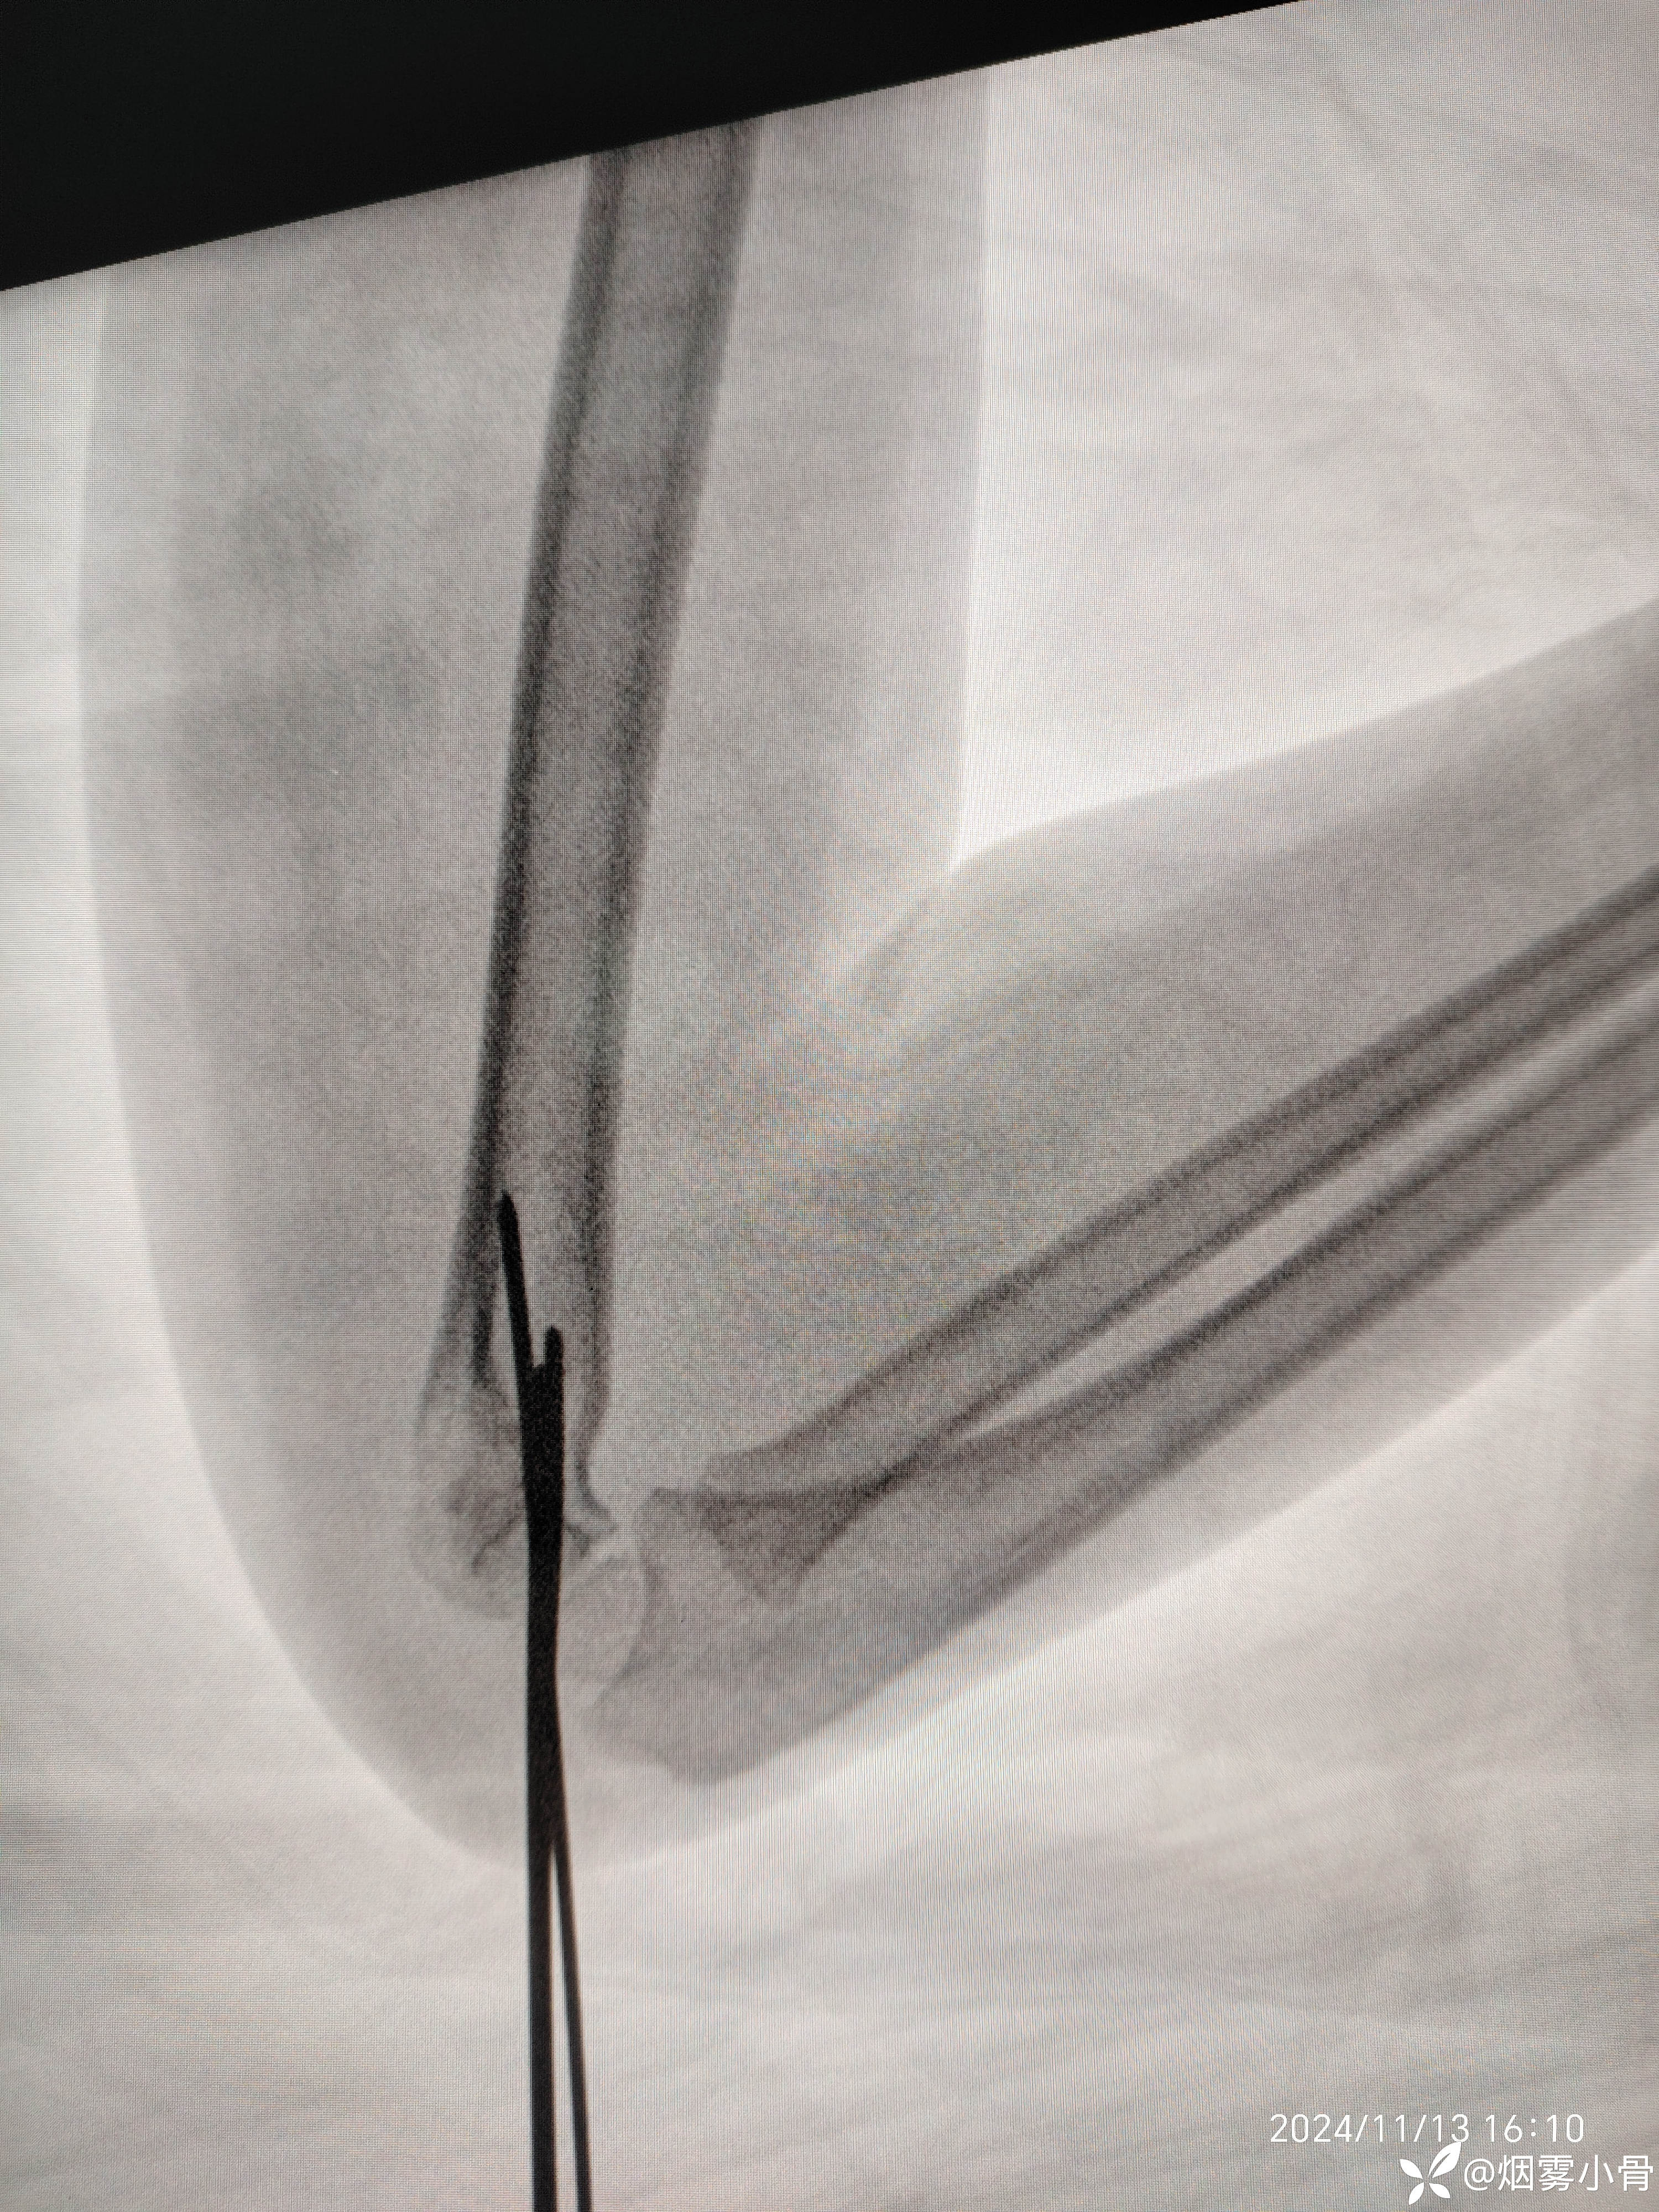

6岁肱骨髁上骨折,急诊30分钟完成零切开闭合复位克氏针内固定

30分钟完成一例肱骨髁上骨折闭合穿针及石膏固定手术,术中透视拍片8张。